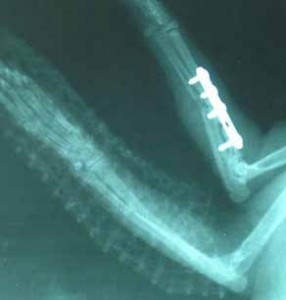

Dne 30.03.2006 se Sisi podrobila operaci, při které byla provedena osteosyntéza, kdy se tato těžká zlomenina fixovala šrouby. Druhou frakturu

fixuje termoplastická dlaha. Sisi se po této těžké operaci velice dobře

zotavila, hned začala baštit a cítila se

dobře, takže naštěstí nebylo nutné kočičku zatěžovat infuzí.

Bohužel, v průběhu rekonvalescence začaly komplikace. V operované pacince

nebylo obnoveno krvení a začalo docházet k otoku a odumírání. Proto jsme

museli přikročit k amputaci celé končetiny, která se provedla dne 04.04.2006.